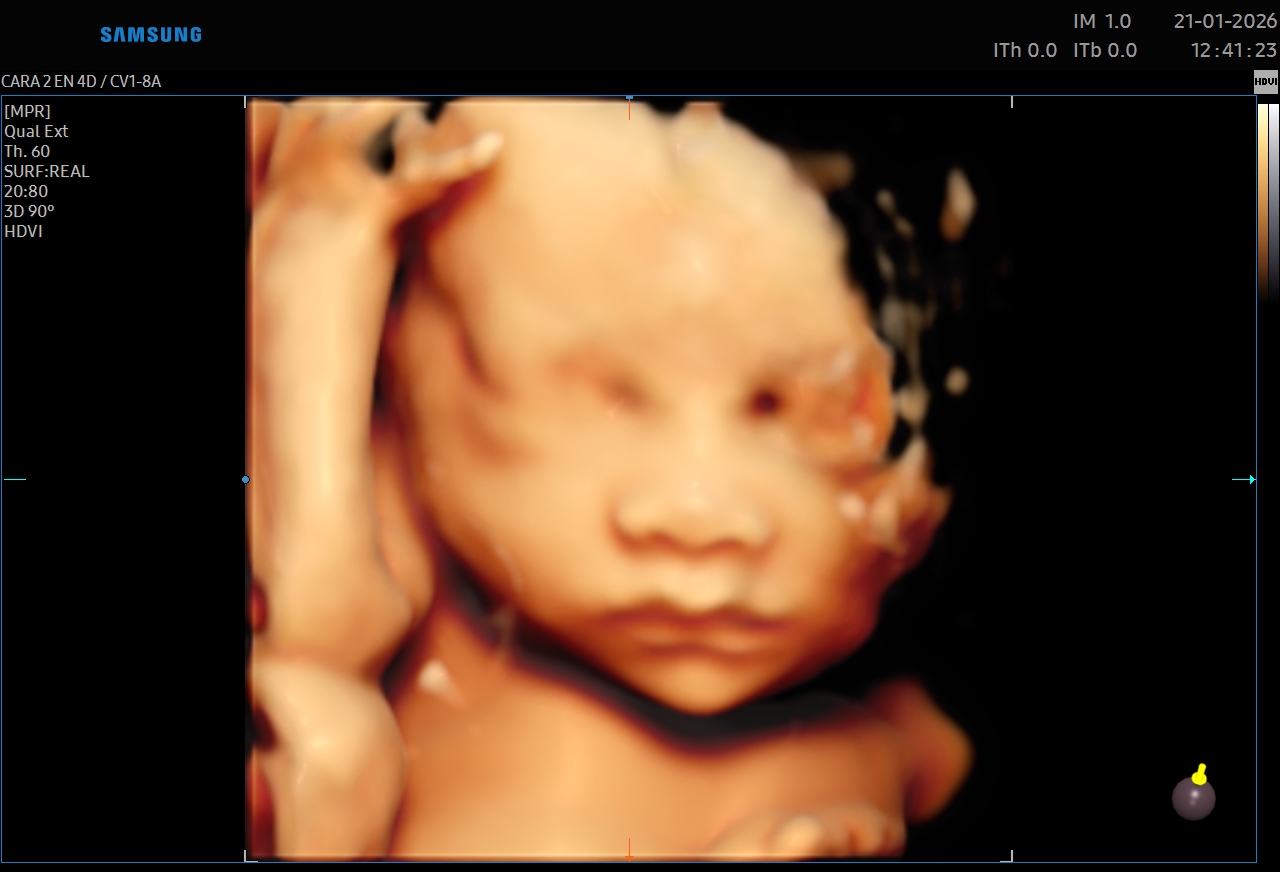

Ecografías 5D

La ecografía 5D es una experiencia única que te permite ver a tu bebé con un nivel de realismo sorprendente, capturando detalles como sus gestos, expresiones y movimientos en tiempo real.

Gracias a esta tecnología avanzada, podrás observar el rostro de tu bebé con mayor claridad, creando un vínculo emocional aún más especial antes de su nacimiento. Es el momento perfecto para compartir con tu familia y guardar recuerdos inolvidables de esta etapa tan importante.

Además de ser una experiencia hermosa, este estudio se realiza con equipos de alta tecnología y bajo supervisión médica, garantizando seguridad tanto para la mamá como para el bebé.